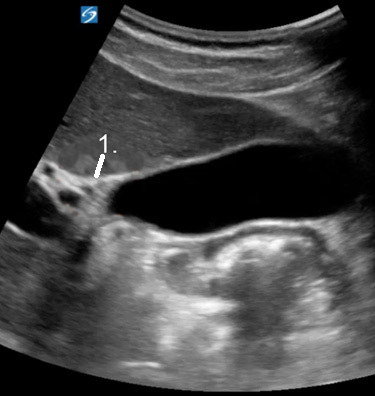

胆嚢主葉裂 (MLF) イメージ

主な大葉裂 (MLF)